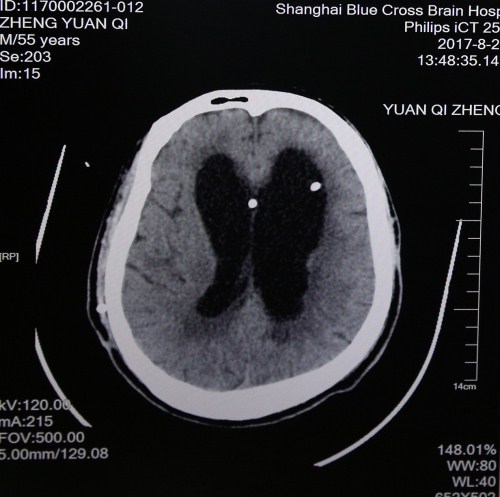

入院初头颅CT影像:之前做过分流手术,置入两分流管,脑室扩大、肿胀、有软化、渗出,脑压高

最近头颅CT影像:脑沟回明显,脑室缩小,脑压降低,重新置管分流后有效